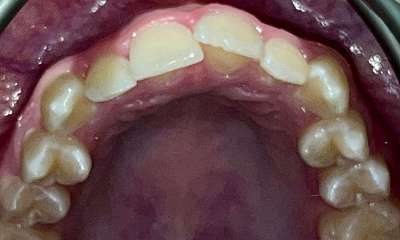

This patient presented with concerns about the damage his teeth had sustained from his bite and previous habits. His lower teeth had caused erosion and wear on the palatal surfaces and incisal edges of his upper front teeth. He was also concerned about the crowding of the lower front teeth. His primary goal was to create a more protected alignment and function of his teeth to support better oral health and longevity.

Due to a sensitive gag reflex, he first trialled nightly whitening trays for two weeks to assess whether he could tolerate aligner wear. This approach gave him the confidence ...